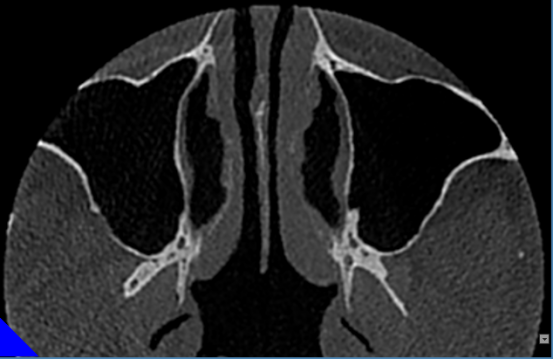

窦部扫描提供窦部综合性判断。